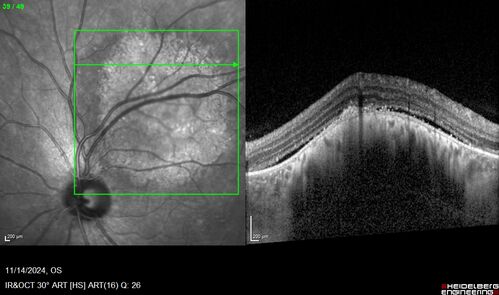

Small choroidal melanoma

28 year old man Serial images suggested that the lesion is growing

OD: sc20/16

OS: sc20/40+2

IOP: TP: OD:19 OS:16